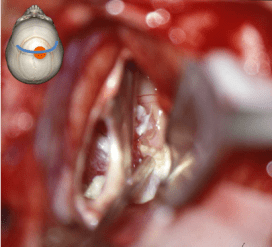

la voie transcalleuse

c’est la voie la plus utilisée car elle nécessite un abord minimal ; l’interruption des fibres du corps calleux sur environ 2 cm n’a pas de conséquence cliniquement perceptible.

de plus, elle permet un accès aux deux ventricules latéraux, sans nécessité de fenestration du septum, ce qui peut être utile pour les tumeurs du V3 volumineuses.

elle a comme inconvénients :

- des adhérences possibles entre les deux hémisphères, surtout en cas de craniopharyngiome ou de tératome (méningite chimique) ou en cas de

protection de la veine pré-centrale par surgicel et colle de fibrine réintervention

- une possible lésion du cortex cingulaire, ou des artères calloso-marginale ou péricalleuse

- une dissection parfois difficile des veines cortico-durales notamment en région pré-centrale ; il est important d’empêcher ces veines de sécher au cours de l’intervention (Cf. ci-contre)